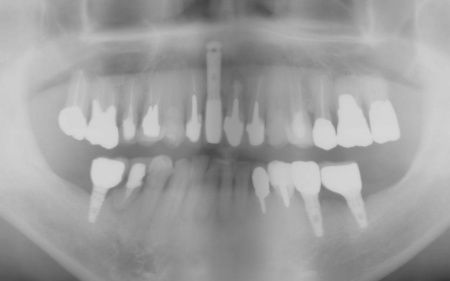

70代男性 右下奥歯を抜いてインプラント治療で噛み合わせを回復した症例

拝見したところ、右下奥歯(第2小臼歯)の周辺組織に炎症が広がり、歯茎が赤く腫れていました。

まず、右下奥歯(第2小臼歯)を抜き、骨が治癒するのを待ってから、インプラントを埋入します。

インプラントと顎の骨がしっかりと結合したら、精密な型取りを行い、インプラント上部に装着する最終的な被せ物を作製しました。

最後に完成した被せ物を装着し、見た目や噛み合わせに問題がないことを確認して、治療を終了しています。